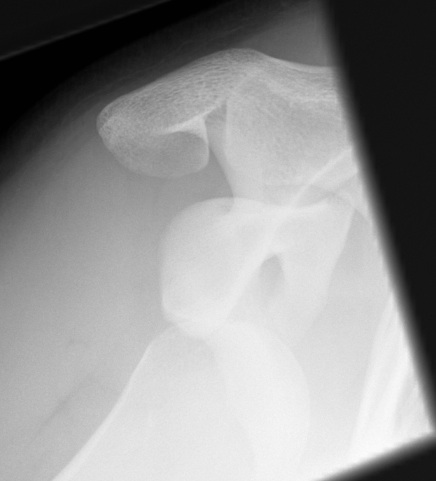

Rare

- 2% of acute dislocations

Often missed

- < 1/ 52 25%

- < 6/52 25%

- < 6/12 25%

- > 6/12 25%

Most common form of shoulder instability

- young males

- M:F = 2:1

Indirect ER and abduction moment on arm

- disruption of anterior stabilisers

Initial injury

- severe pain in shoulder